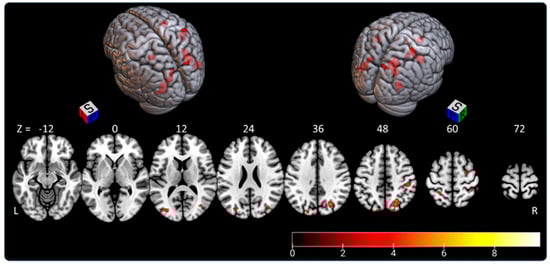

3.1. Subjective Straight-Ahead Task (SSA)

- the right parietal lobe (superior parietal lobule: A7c, A5l, A7pc; inferior parietal lobule: A39c, A40rd, A40rv; precuneus: dmPOS; postcentral gyrus: A2) representing 45.5% of activated areas;

- the right lateral occipital cortex (msOccG, lsOccG, mOccG), representing 21.5% of activated areas;

- the left lateral occipital cortex (V5/MT+, msOccG, lsOccG, mOccG), representing 16% of activated areas;

- the left parietal lobe (superior parietal lobule: A5l, A7pc; and inferior parietal lobule: A39c), representing 9.5% of activated areas; and

- the right premotor cortex (superior frontal gyrus: A6cdl), representing 7.5% of activated areas.

| Cluster Voxels/Side | AAL3 % in the Area | Peak MNI Coordinates (x y z)/T Value | Brainnetome % in the Area |

|---|---|---|---|

| 226/right | 42.5 occipital sup 33.6 parietal sup | 24 −62 46/5.630 | 31.9 lsOccg 28.8 A7c |

| 92/left | 96.7 occipital mid | −30 −84 14/5.023 | 44.6 mOccG |

| 35.9 A39c | |||

| 81/right | 61.7 postcentral | 46 −28 42/5.440 | 69.1 A40rd |

| 29.6 supramarginal | 19.8 A2 | ||

| 66/right | 87.9 occipital mind | 42 −80 18/5.471 | 54.5 A39c 31.8 mOccG |

| 58/right | 55.2 postcentral 25.9 parietal inf 19.0 parietal sup | 38 −44 66/5.216 | 12.1 A7pc 60.3 A5l 19.0 A7ip |

| 40/right | 72.5 frontal sup 17.5 precentral | 26 −4 58/5.087 | 85.0 A6cdl 10.0 A6dl |

| 39/left | 76.9 occipital sup 23.1 parietal sup | −18 −86 38/4.506 | 10.3 msOccG 79.5 lsOccG |

| 31/left | 51.6 parietal sup | −26 −46 58/6.259 | 19.4 A7pc |

| 25.8 parietal inf 22.6 postcentral | 38.7 A5l |